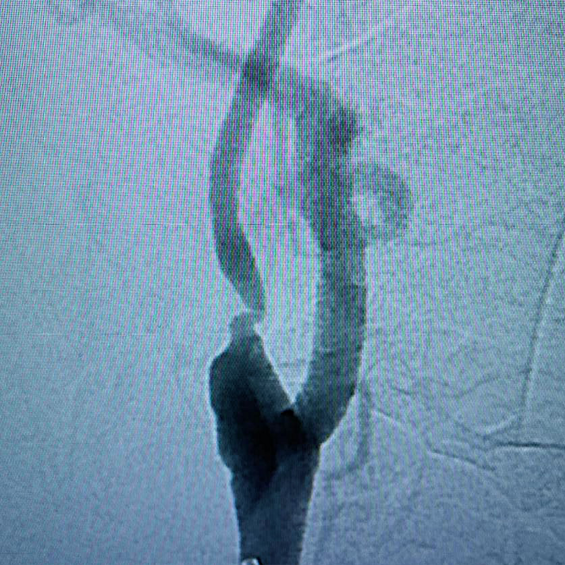

Desobstrução de Artérias Carótidas